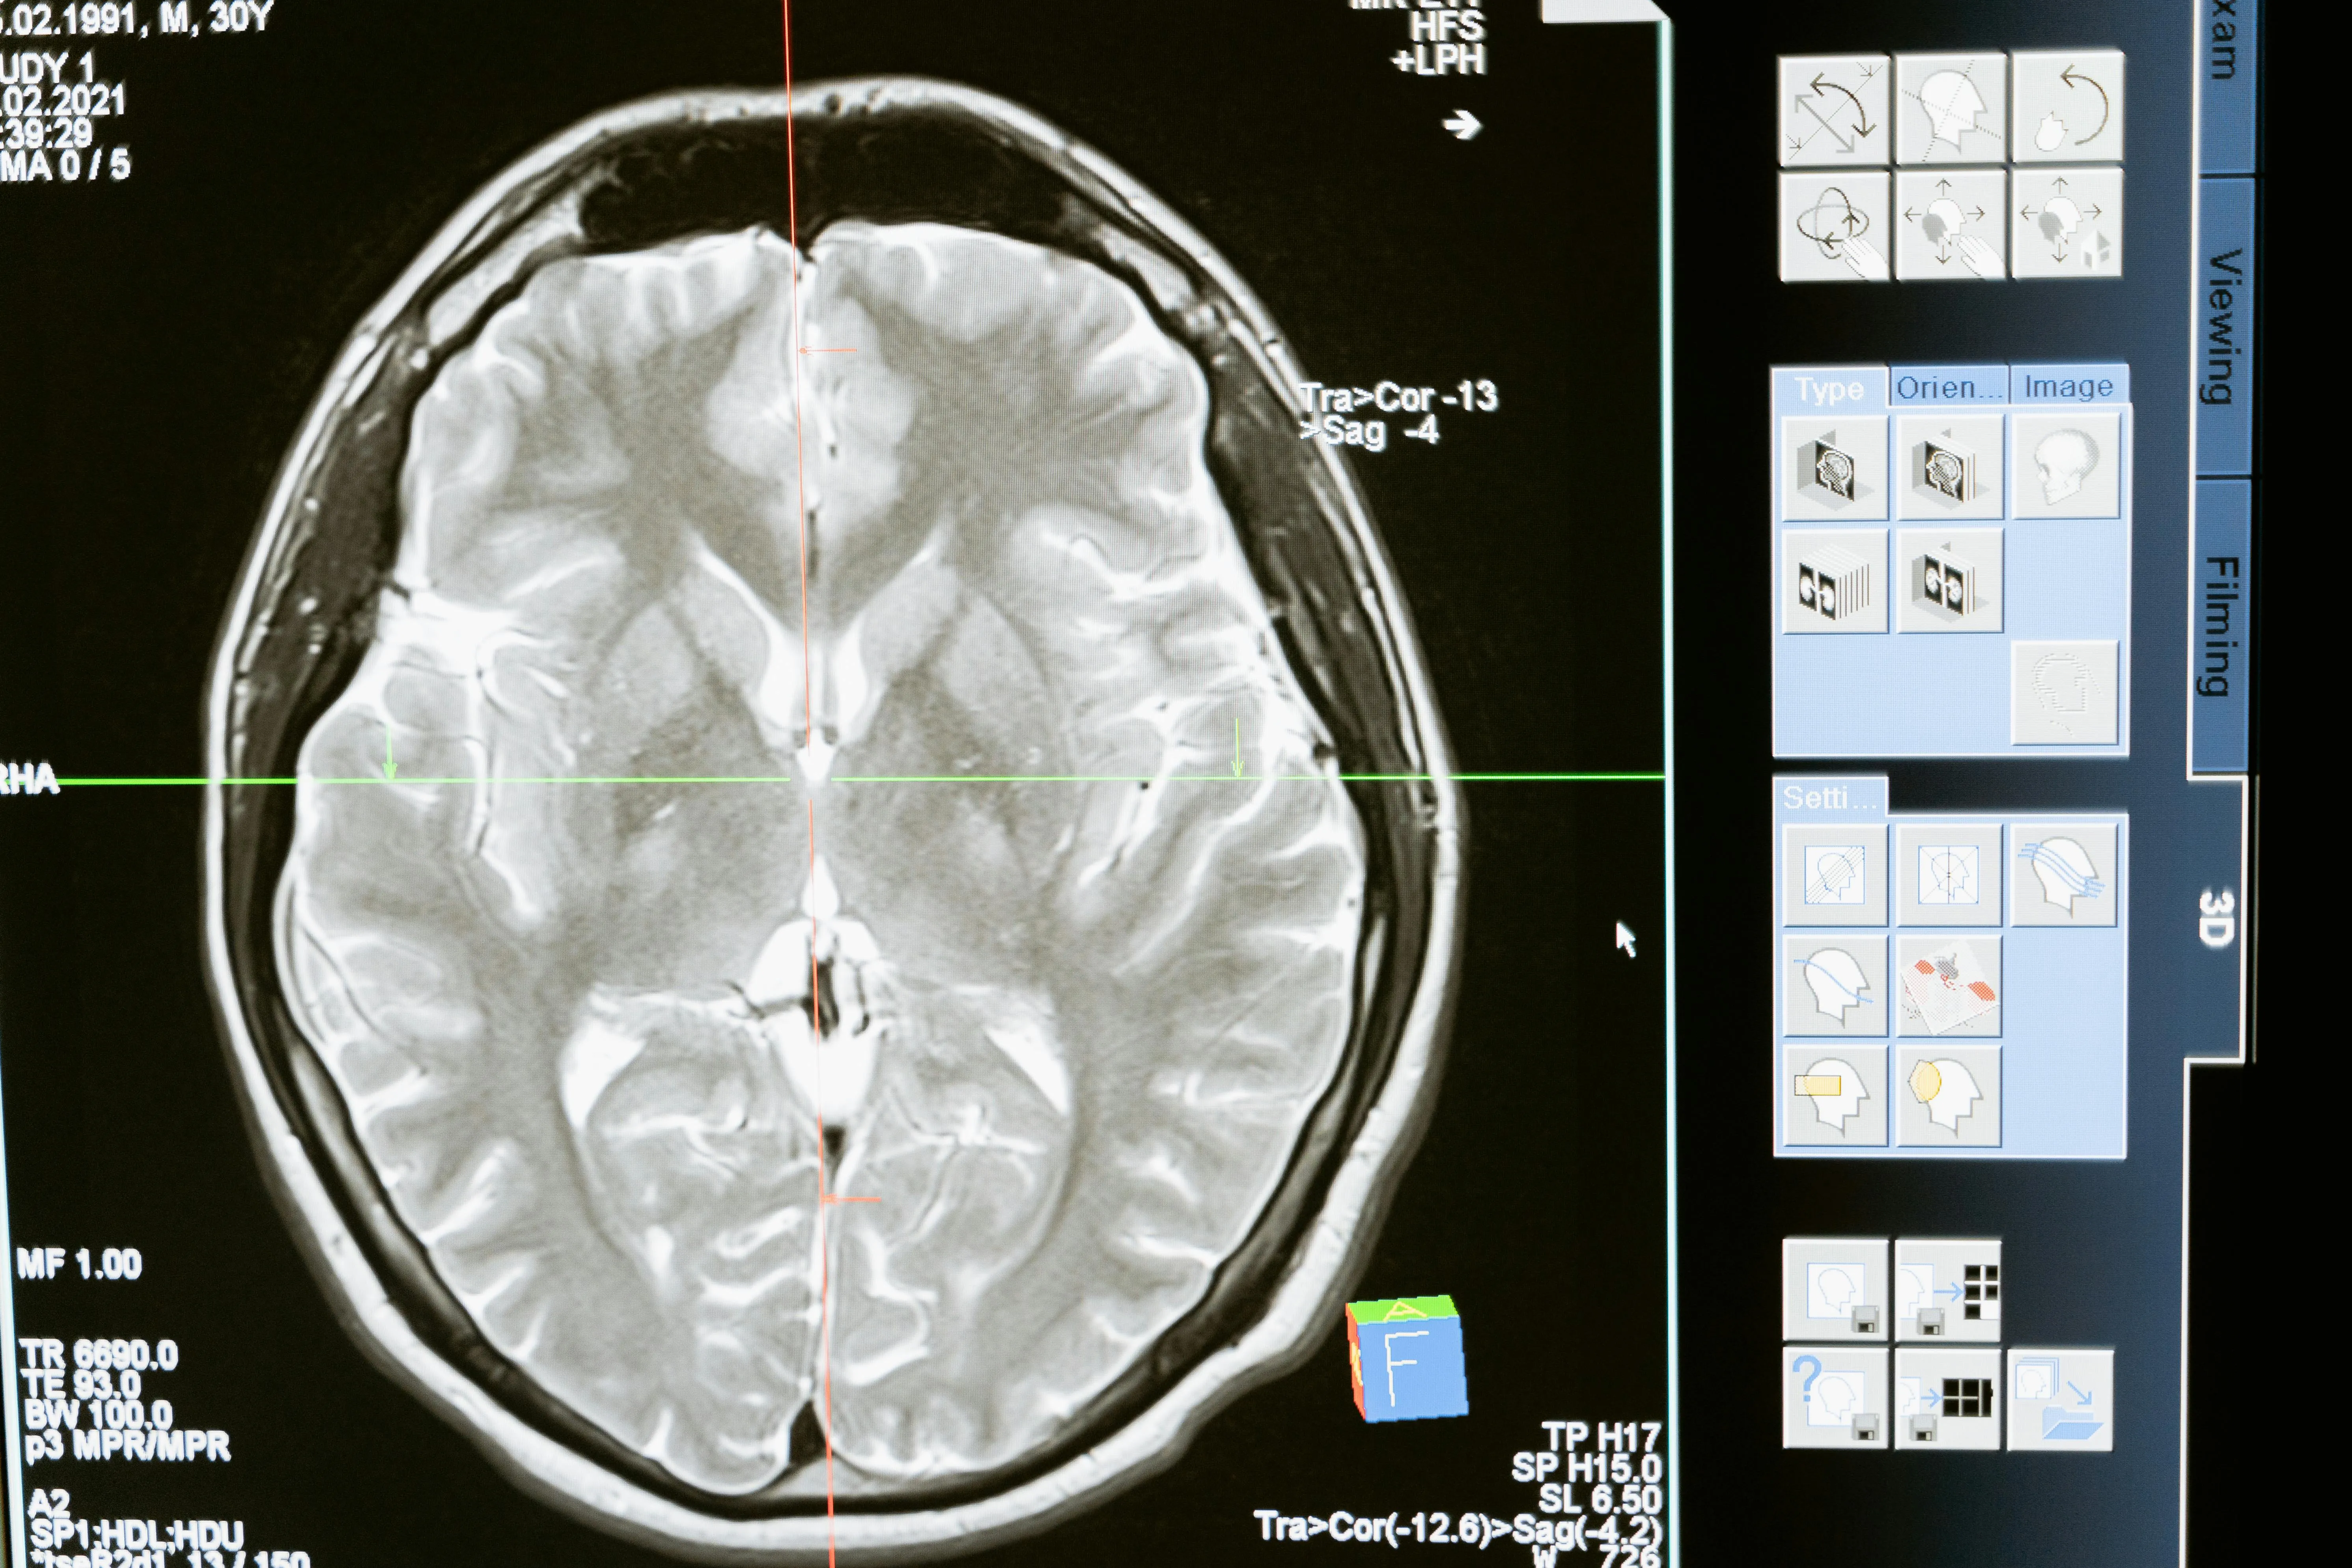

우리나라에서 흔히 발생하는 뇌혈관 질환 중 하나가 바로 뇌경색입니다. 뇌경색은 뇌혈관이 막히면서 혈액 공급이 원활하지 않아 뇌세포가 손상되는 질환인데요. 중요한 점은 뇌경색 초기증상을 빨리 발견하느냐에 따라 후유증과 생존율이 크게 달라진다는 것입니다. 오늘은 많은 분들이 궁금해하는 뇌경색 초기증상과 대처 방법에 대해 자세히 알아보겠습니다. 지금 알려드리는 대처법은 혼자 알고 있어도 되지만 주변 가족분들이 알고 있으면 더 좋겠죠?

뇌경색은 발병 직후 몇 시간 내에 치료를 시작해야 뇌 손상을 최소화할 수 있습니다. 뇌경색 초기증상을 놓치면 치료 골든타임을 놓쳐 반신마비, 언어장애, 기억력 저하와 같은 심각한 후유증이 남을 수 있습니다. 따라서 작은 변화라도 놓치지 않고 즉시 병원을 찾는 것이 생명을 지키는 길입니다.